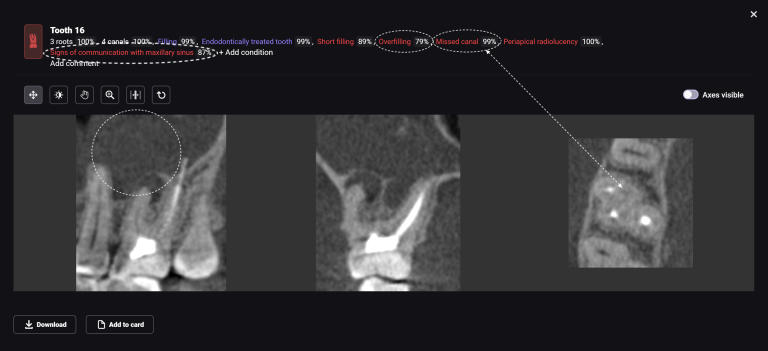

Extracting upper third molars can be difficult, if they are impacted and in contact with the maxillary sinus. Diagnocat AI will help you carefully plan your procedure, minimizing the risk of possible complications.

The “Third Molar Report” is a tool created by Diagnocat AI, it creates an optimal 3D visualization which helps to assess the position of the roots of the third molars relative to the roots of adjacent teeth and the floor of the maxillary sinus.